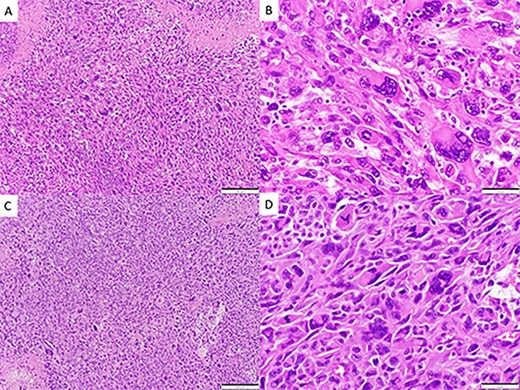

CASE

CT and MRI scans of the head indicating a large hemorrhagic enhancing lesion in the left frontal lobe with surrounding edema causing a rightward midline shift.